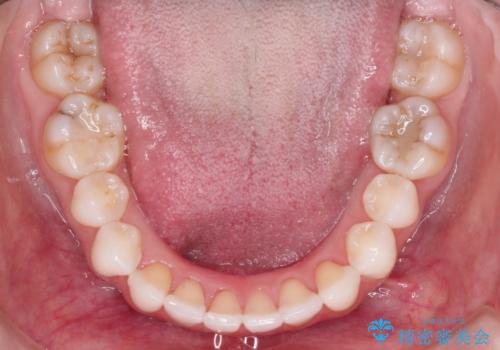

八重歯をマウスピース矯正で治療し、レーザーホワイトニングを行った症例

- 主訴:「右上犬歯を引っ込めて、歯並びをキレイにしたい」

右上の八重歯を気にされてご来院されました。結婚式を控えていたため挙式にまでに可能な限りキレイにしたいとのことでした。

また、ホワイトニングも一緒にご希望されたため、挙式のタイミングに合わせてレーザーホワイトニングを施術させていただきました。

右上の犬歯の歯茎は矯正前から退縮を起こしていましたが、矯正後もその退縮に関しては変化がありませんでした。今回は患者様が歯肉退縮に関しては治療をご希望ではありませんでしたが、当院ではこのように歯茎が下がり露出した根面を、歯茎を移植することでカバーし見た目を改善する手術を行っています。